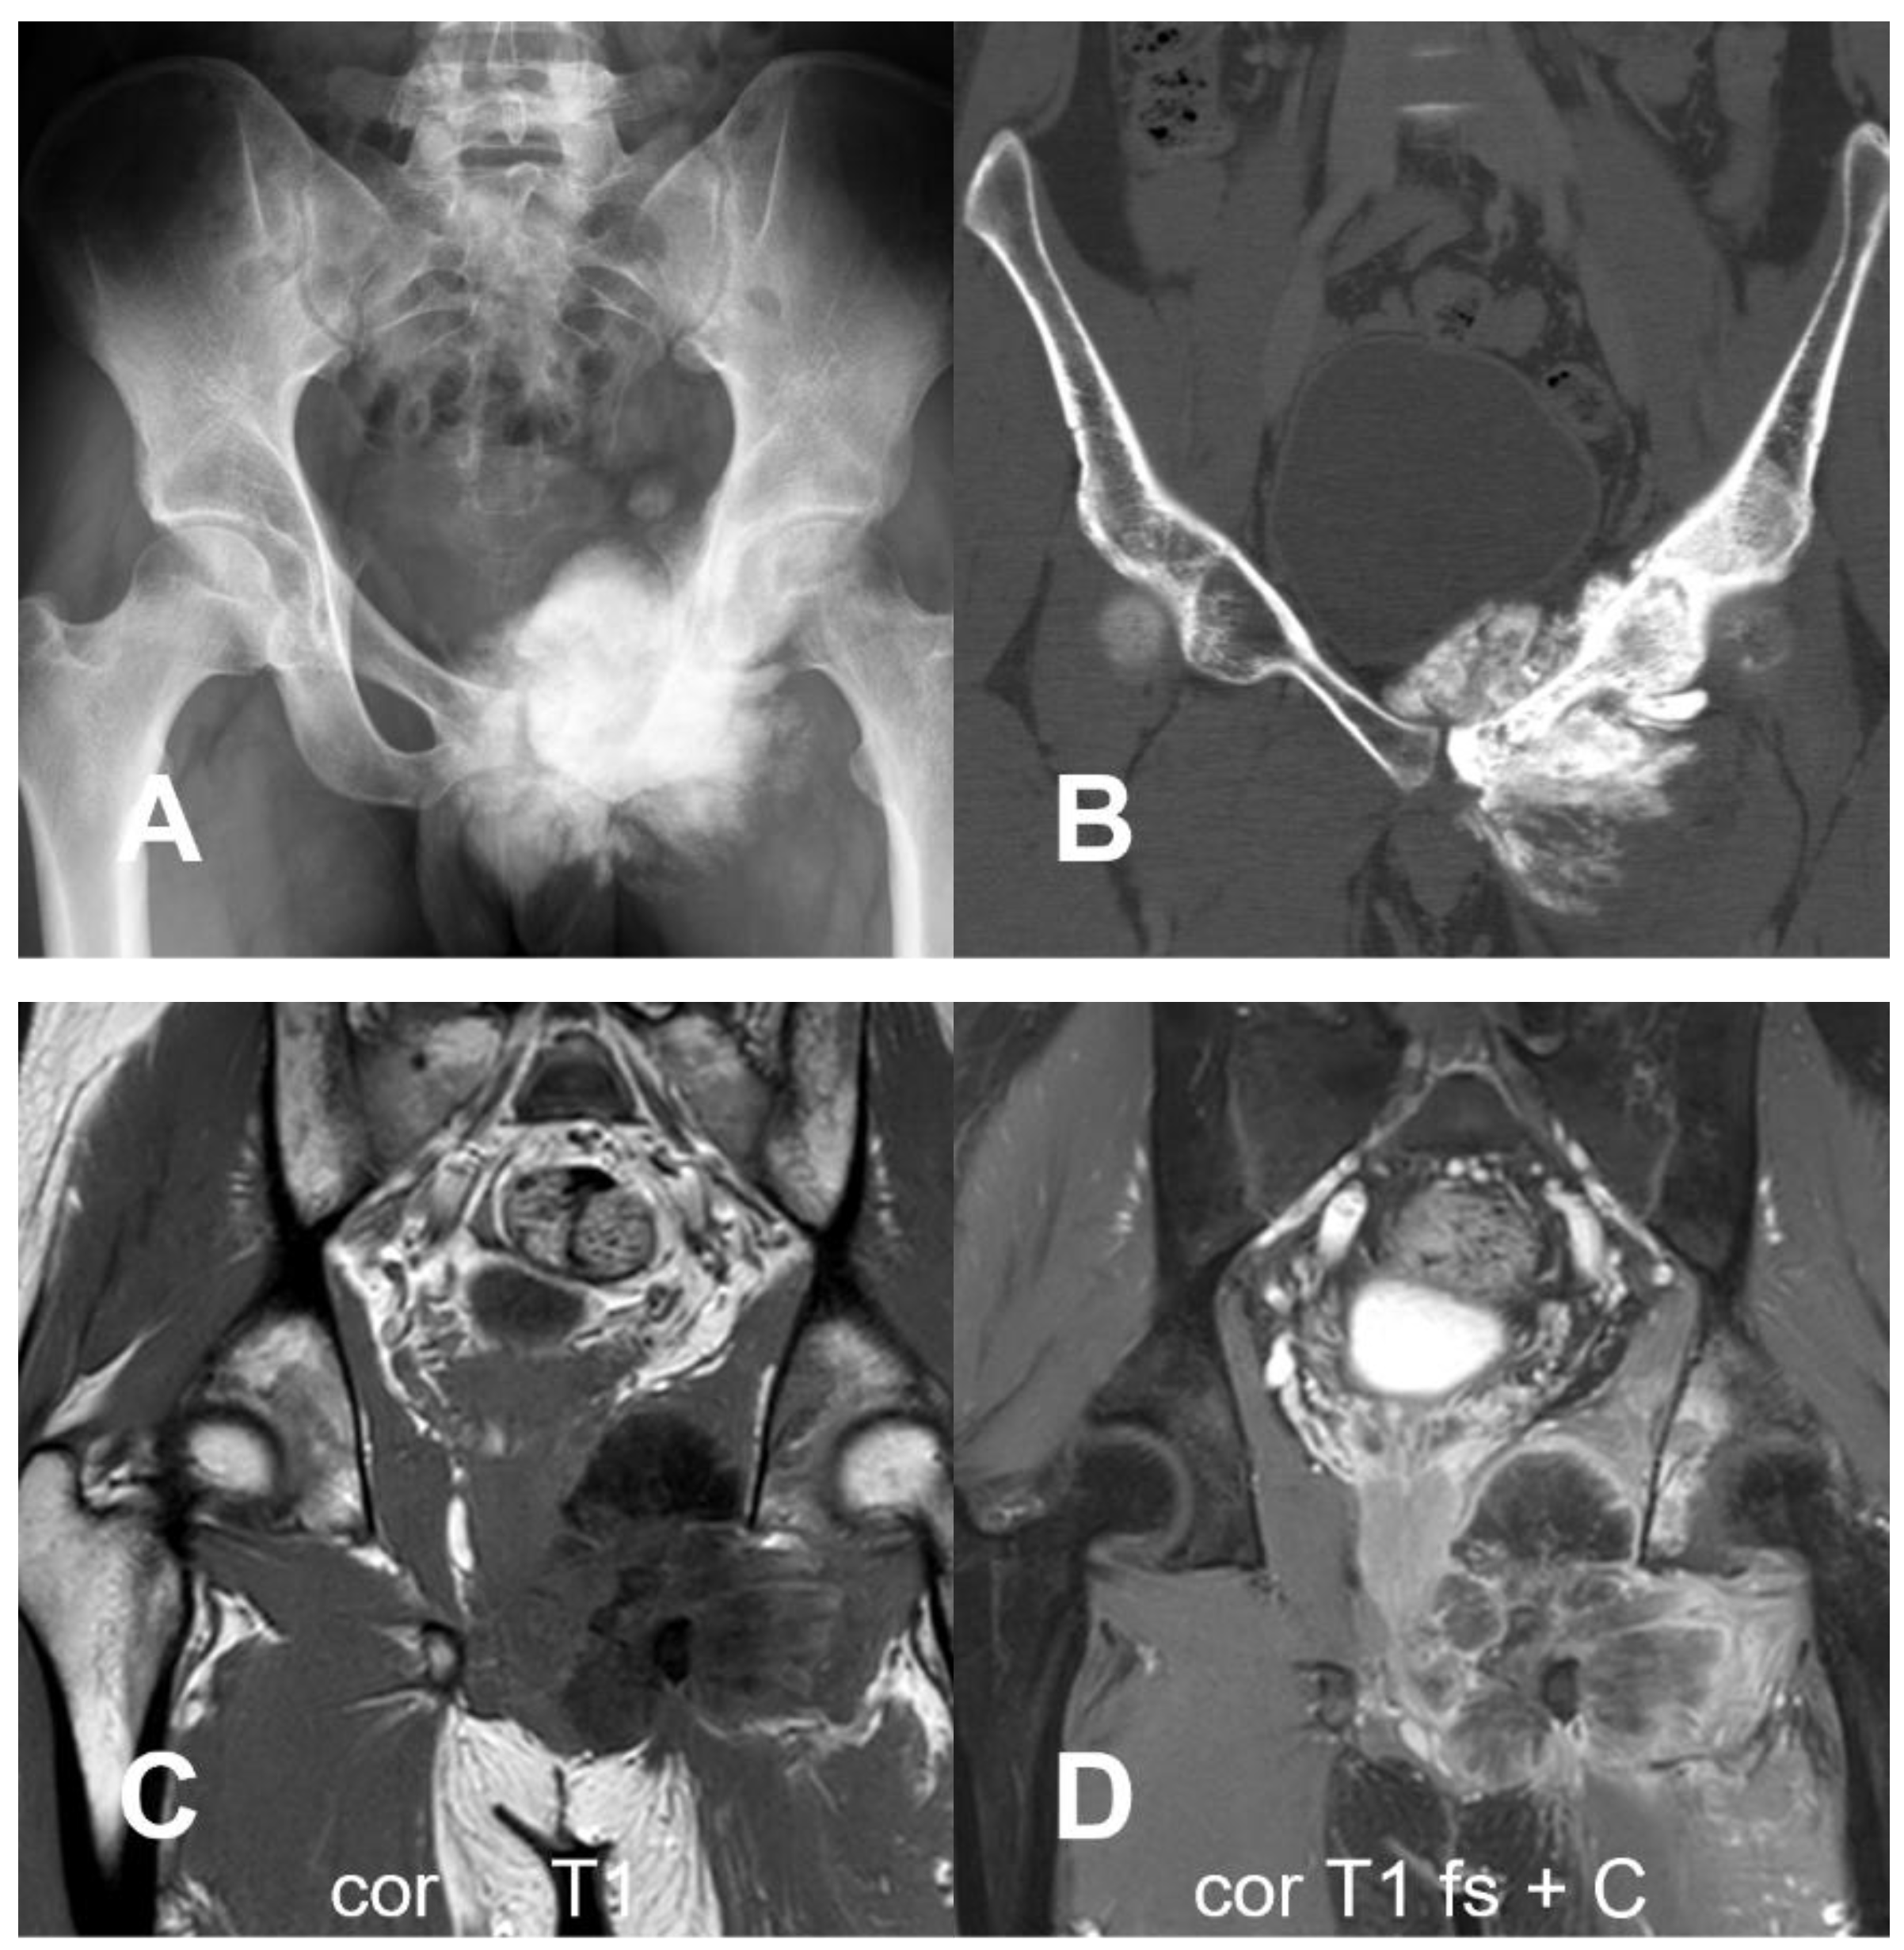

3.1.2. Secondary Osteosarcoma

- Meazza, C.; Giovanna, S.; Nigro, O.; Gattuso, G.; Francesco, B.; Podda, M.; Luksch, R.; Biassoni, V.; Schiavello, E.; Ferrari, A.; et al. Secondary Osteosarcoma: A Challenge Indeed. Int. J. Clin. Oncol. 2023, 28, 184–190. [Google Scholar] [CrossRef] [PubMed]

- Hansen, M.F.; Seton, M.; Merchant, A. Osteosarcoma in Paget’s Disease of Bone. J. Bone Miner. Res. 2006, 21, P58–P63. [Google Scholar] [CrossRef] [PubMed]

- Dray, M.S.; Miller, M.V. Paget’s Osteosarcoma and Post-Radiation Osteosarcoma: Secondary Osteosarcoma at Middlemore Hospital, New Zealand. Pathology 2008, 40, 604–610. [Google Scholar] [CrossRef] [PubMed]

- Nakashima, H.; Takatsu, T.; Imai, R. Radiation-Induced Osteosarcoma in the Pubic Bone after Proton Radiotherapy for Prostate Cancer: A Case Report. J. Rural Med. 2022, 17, 2021–2047. [Google Scholar] [CrossRef] [PubMed]